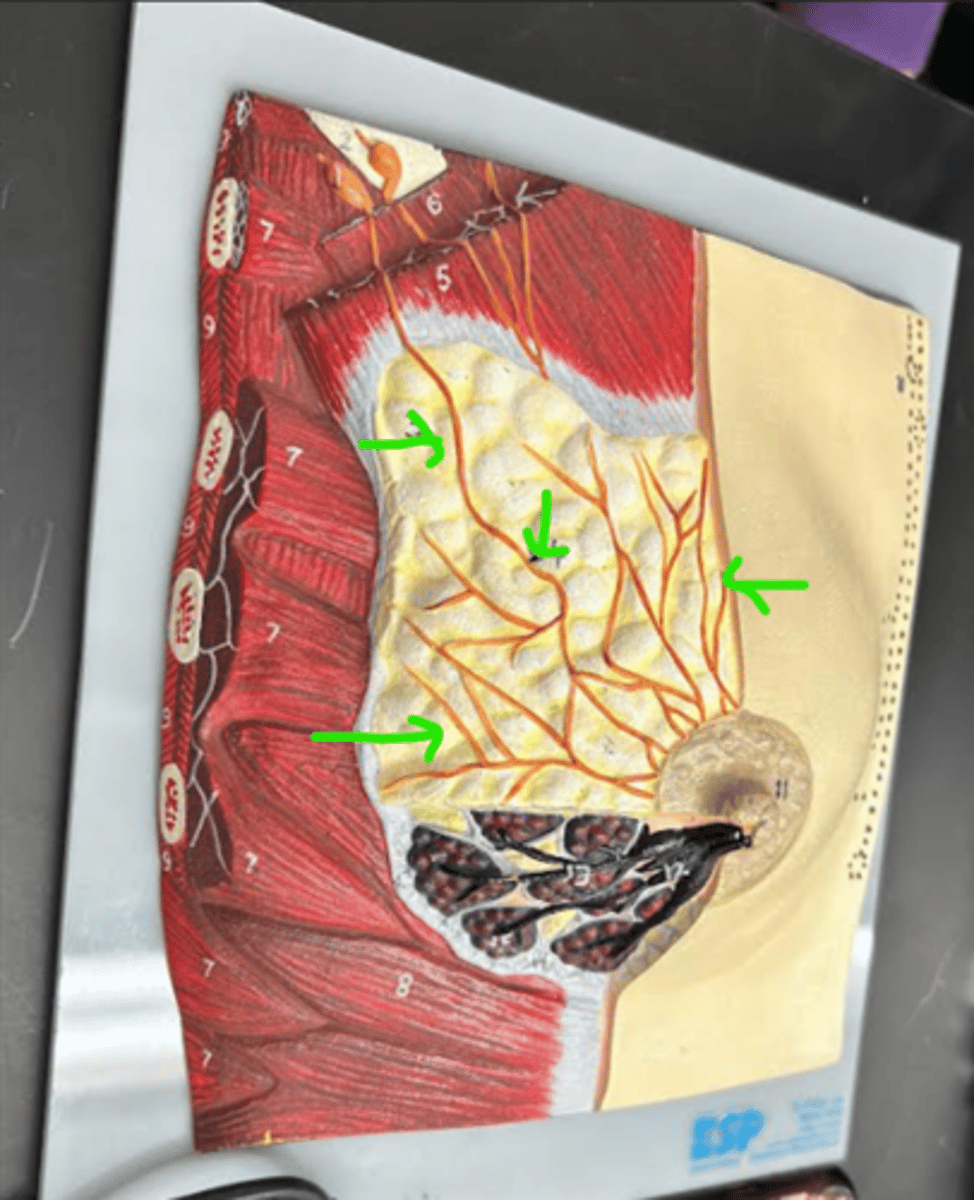

Breast

whole structure/ model

Axillary tail

Areola

Nipple

Suspensory ligament

Adipose tissue

Lactiferous sinus

Lactiferous duct

Mammary lobe

Mammary lobule